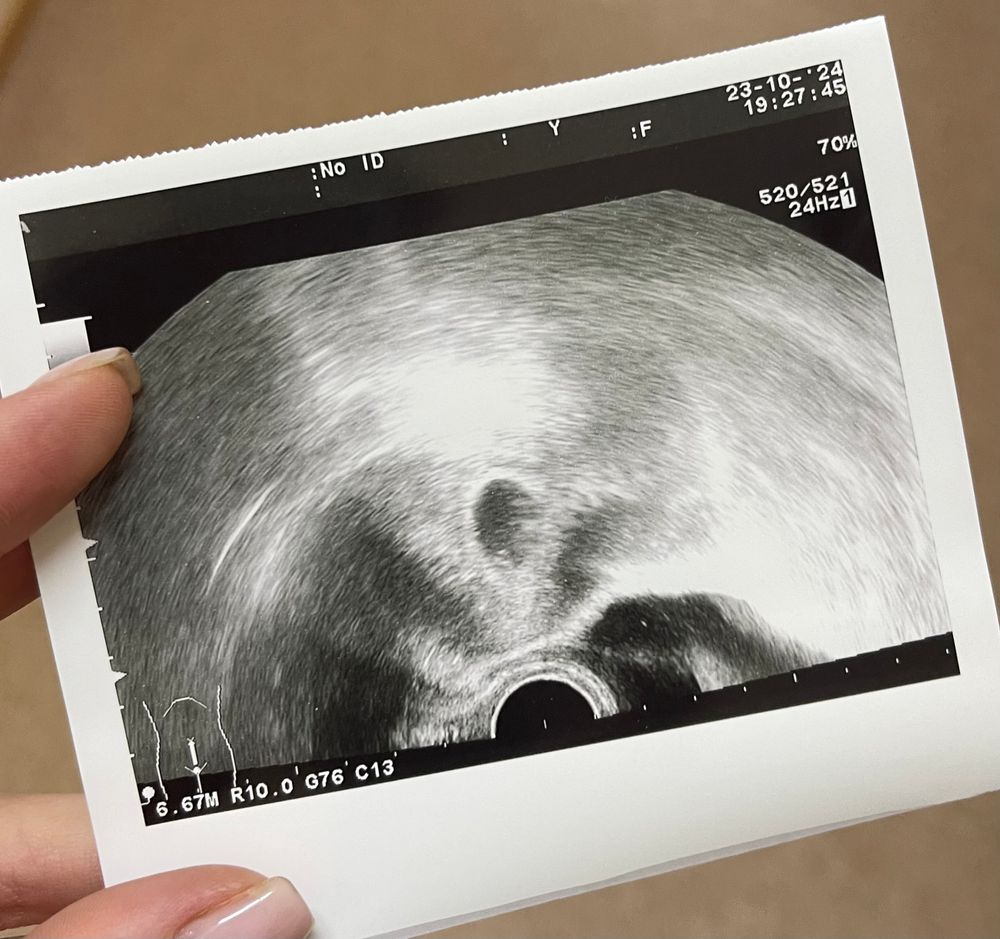

Первое узи 22 дпп🥰

УЗИ 28 дпп 28дпп и первое узи 💍🥹